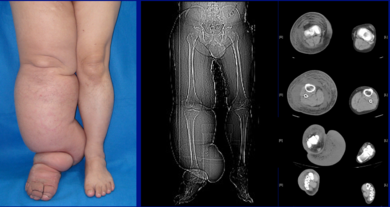

| Lower extremity lymphedema | |

The most common manifestation of lymphedema is soft tissue swelling, edema. As the disorder progresses, worsening edema and skin changes including discoloration, verrucous (wart-like) hyperplasia, hyperkeratosis, papillomatosis, dermal thickening, and ulcers may be seen. Additionally, there is increased risk of infection of the skin, known as Erysipelas.

- Grade 3: Gross increase in volume and circumference of Grade 2 lymphedema, with eight stages of severity given below based on clinical assessments.

- Stage 3: Swelling is irreversible and usually the limb(s) or affected area becomes increasingly large. The tissue is hard (fibrotic) and unresponsive; some patients consider undergoing reconstructive surgery, called "debulking". This remains controversial, however, since the risks may outweigh the benefits and the further damage done to the lymphatic system may in fact make the lymphedema worse.

- Stage 4: The size and circumference of the affected limb(s) become noticeably large. Bumps, lumps, or protrusions (also called knobs) on the skin begin to appear.

- Stage 5: The affected limb(s) become grossly large; one or more deep skin folds is prevalent among patients in this stage.

- Grade 4 (gigantic edema): In this stage of lymphedema, the affected extremities are huge, due to almost complete blockage of the lymph channels.